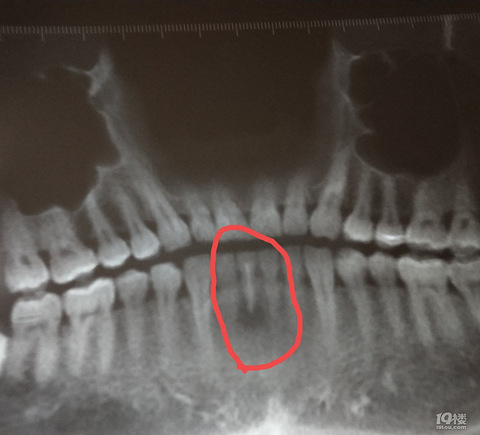

【港港厢】根管治疗的牙齿会不会有什么不良后果?

牙齿被石子硌动,医生给用根管治疗。治完之后,再次给拍片:说看牙补好了没有,别补漏了。但拍片后,说看牙齿根部的黑色,牙齿发炎,,半年后再来检查。这里有几个问题,让人不明白:第二次拍片,说是检查牙补好没有,但拍了片却不提了,而却是说牙根发炎。牙根发炎的话,问题是为何不痛?不用吃消炎药吗?这发炎,等半年自己会痊愈了?或者不痊愈,半年后又怎么办?根管治疗的牙齿,会好吗?或者会留下什么隐患吗?